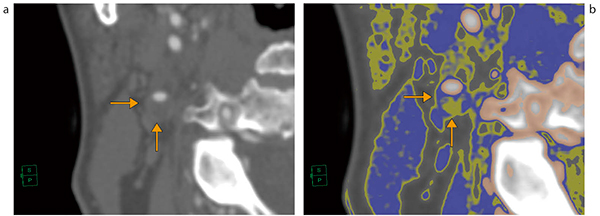

図1 総頸動脈セグメンテーションとCPR表示

狭窄部位では,CPR機能により血管の直交方向のCT画像(オブリーク)を再構築し,狭窄部の血管壁を観察する。グレイスケールでは判定できないような微妙なコントラストの場合は,クリアウインドウ機能で微細なコントラスト変化をカラーリングによってとらえ,CT値によるプラークの評価を容易にする(クリアウインドウ機能は特許取得ずみ)(図2)。

図2 狭窄部位の血管直交断面とカラーリング表示

微細なCT値変化をとらえることができる。